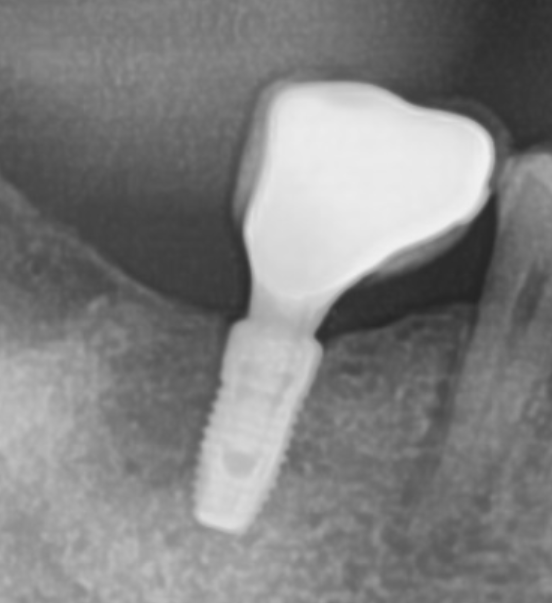

흔들리는 임플란트 치료 사례

임플란트를 심고 나서도 생길 수 있는 문제가 흔들리는 경우입니다.

일반적으로 임플란트가 흔들리는 가장 흔한 경우는

임플란트의 내부의 나사가 풀렸기 때문입니다.

임플란트 내부 나사가 풀리는 것을 대수롭지 않게 생각하고

방치하게 되면 세균으로 인해 더 큰 문제가 발생할 수 있습니다.